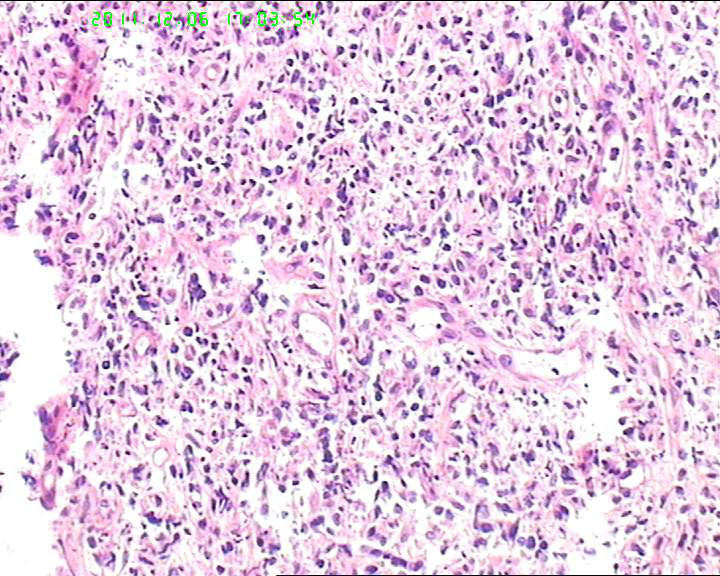

细胞异性明显,弥散分布,可见血管内皮异性明显,首先考虑血管肉瘤,恶黑,淋巴瘤?

组织内见大量形态各异的异型明显的细胞,弥漫分布,背景见肿瘤素质,首先考虑结外NK/T细胞淋巴瘤,鼻型;恶黑待排。